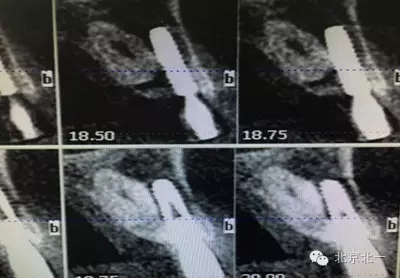

患者種植一月后種植區(qū)不適,偶有疼痛來院拍片發(fā)現(xiàn)23埋伏牙,與種植體相鄰,如圖一、二、三、四所示。